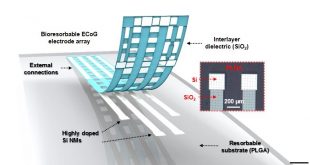

ادامهی نوشتهساخت نسل آینده الکترودها: پایش مغز با کاشتهای الکترونیکی-سیلیکونی قابل انعطاف و تجزیه پذیر

این محتوا صرفا برای کاربران ویژه سایت در نظر گرفته شده است. اگر میخواهید به آن دسترسی داشته باشید به جمع کاربران ویژه سایت بپیوندید: لینک ورود به جمع کاربران ویژه